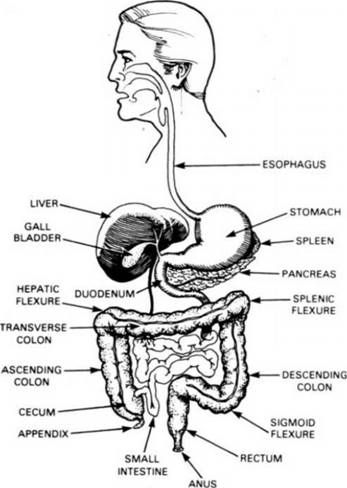

Study sketch.

THIS IS AN OUTLINE OF THE DIGESTIVE SYSTEM

Food enters the mouth, goes down the esophagus and enters the stomach. The pyloric valve controls the passage of food from the stomach to the duodenum, where the bile and the pancreatic juices continue the processing.

From the duodenum the food travels through the small intestine from which liquefied nourishment goes to the liver. What cannot be digested is propelled to the ascending colon as waste. As debris and as feces for evacuation from the system.